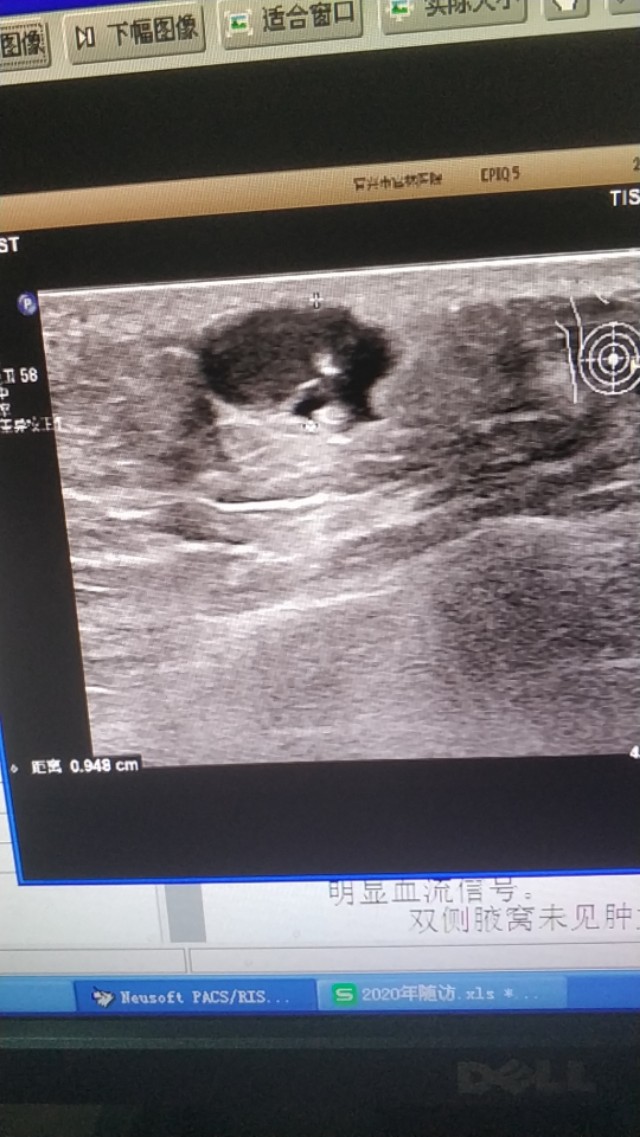

上图是一个左膝部的表皮囊肿,与皮肤真皮层关系密切,里面回声细密伴裂隙样低回声。